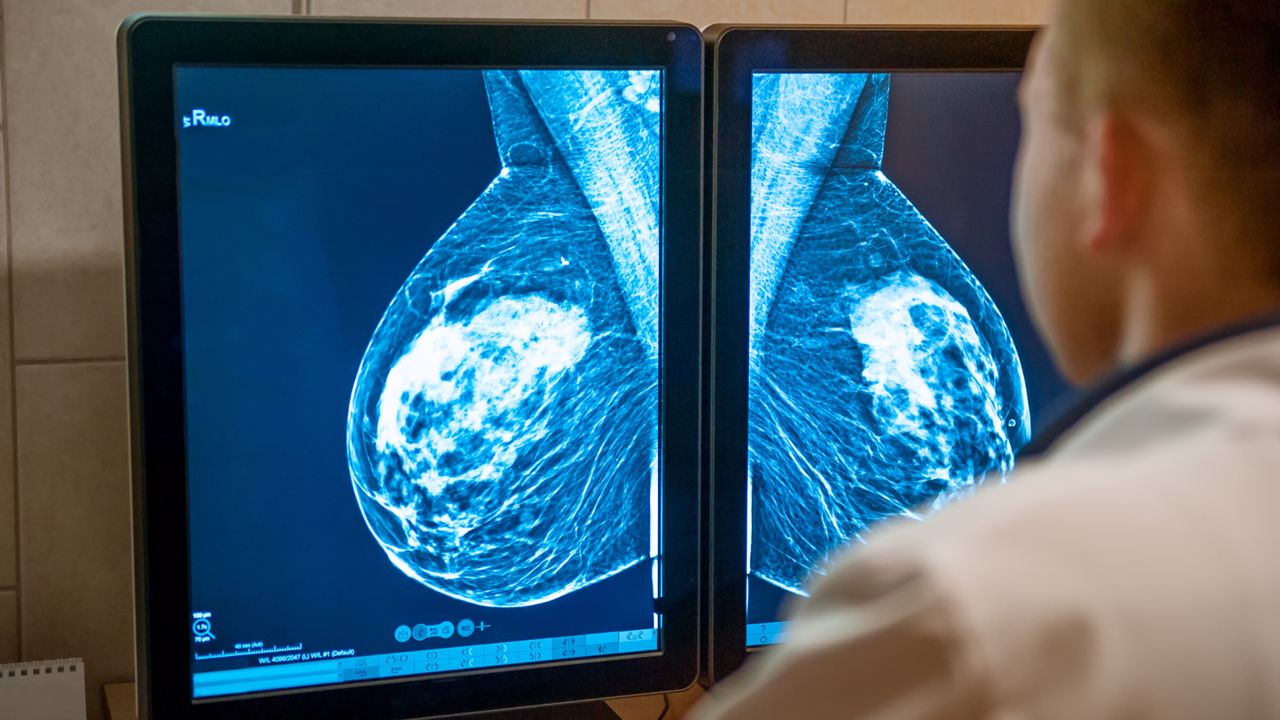

Las formas no invasivas de la neoplasia son las que no se expanden más allá de la mama (carcinoma in situ) y son más fáciles de detectar sólo con la mamografía, ya que a menudo no dan lugar a bultos palpables.

Hay que recordar que la autoexploración no puede ni debe sustituir en modo alguno a las pruebas y exámenes regulares, como la mamografía, que puede detectar bultos u otras microcalcificaciones con extrema precisión.

El método más eficaz en la actualidad para la detección precoz del cáncer de mama es la mamografía. La ecografía también puede ser un examen muy útil, sobre todo para las mujeres que aún son jóvenes.